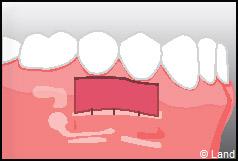

Les greffes épithélio-conjonctives :

Elles sont pratiquées pour des zones non esthétiques de la cavité buccale, à cause de l’aspect « rustine» que la cicatrisation leur confère.

Destinées aux zones esthétiques, elles consistent à prélever la partie profonde du palais (site donneur).